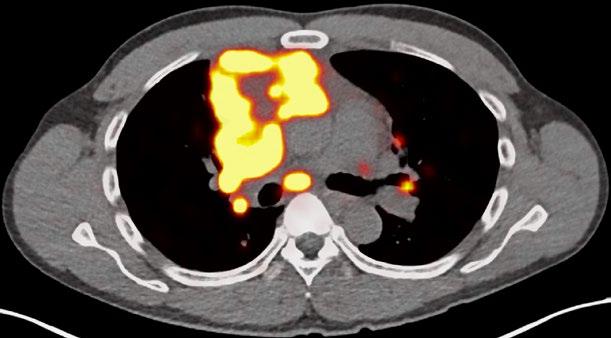

The researchers report on their work in “Tissue-based T cell activation and viral RNA persist for up to 2 years after SARS-CoV-2 infection” published as the cover story in Science Translational Medicine (Vol. 16, No. 754).

First author Michael Peluso, MD, and senior authors Henry F. VanBrocklin, PhD, and Timothy Henrich, MD, in collaboration with a team of multidisciplinary researchers, used whole-body positron emission tomography (PET) imaging with the innovative radiopharmaceutical agent [18F]F-AraG from Cellsight Technologies. This agent is pivotal in mapping activated T lymphocytes in the body, providing a unique insight into immune responses following SARS-CoV-2 infection. The study included a cohort of 24 participants, imaged between 27 to 910 days post-infection, offering a broad perspective on the temporal dynamics of Long Covid.

Imaging Long COVID. The cover shows severe acute respiratory syndrome coronavirus 2 (SARSCoV-2) spike protein–encoding single-stranded RNA (ssRNA, green) in rectosigmoid tissue collected from an individual with Long COVID nearly 2 years after their acute SARS-CoV-2 infection. Nuclei are shown in blue. Peluso et al. performed whole-body positron emission tomography imaging with a tracer that tags activated T cells in a cohort of 24 individuals up to 910 days after acute SARS-CoV-2 infection. The authors found that individuals with Long COVID symptoms had more tracer uptake than those without symptoms, including in the gut. Further, rectosigmoid tissue collected from five participants with Long COVID consistently harbored SARS-CoV-2 spike protein-encoding ssRNA. These data suggest that ongoing T cell activation and viral persistence may be drivers of Long COVID.

The study results are compelling. Participants with postacute COVID-19 exhibited heightened [18F]F-AraG uptake compared to pre-pandemic controls in several anatomical regions, notably the brain stem, spinal cord, bone marrow, lymphoid tissues, cardiopulmonary areas, and the gut wall. This elevated uptake highlights increased T cell activation, a marker of immune system engagement.

Interestingly, T cell activation in the spinal cord and gut wall was closely linked with LC symptoms. Persistent pulmonary symptoms correlated with increased lung tissue activation. These observations were consistent even in participants without overt LC symptoms, indicating a broader immune response pattern post-infection.

In a subset of five participants with LC symptoms, colorectal tissue analysis revealed the presence of SARSCoV-2 RNA. Single-stranded spike protein-encoding RNA was detected in the rectosigmoid lamina propria tissue of all five participants, with double-stranded RNA found in three. This finding, observed up to 676 days post-infection, suggests a potential link between viral persistence and long-term immune disturbances.